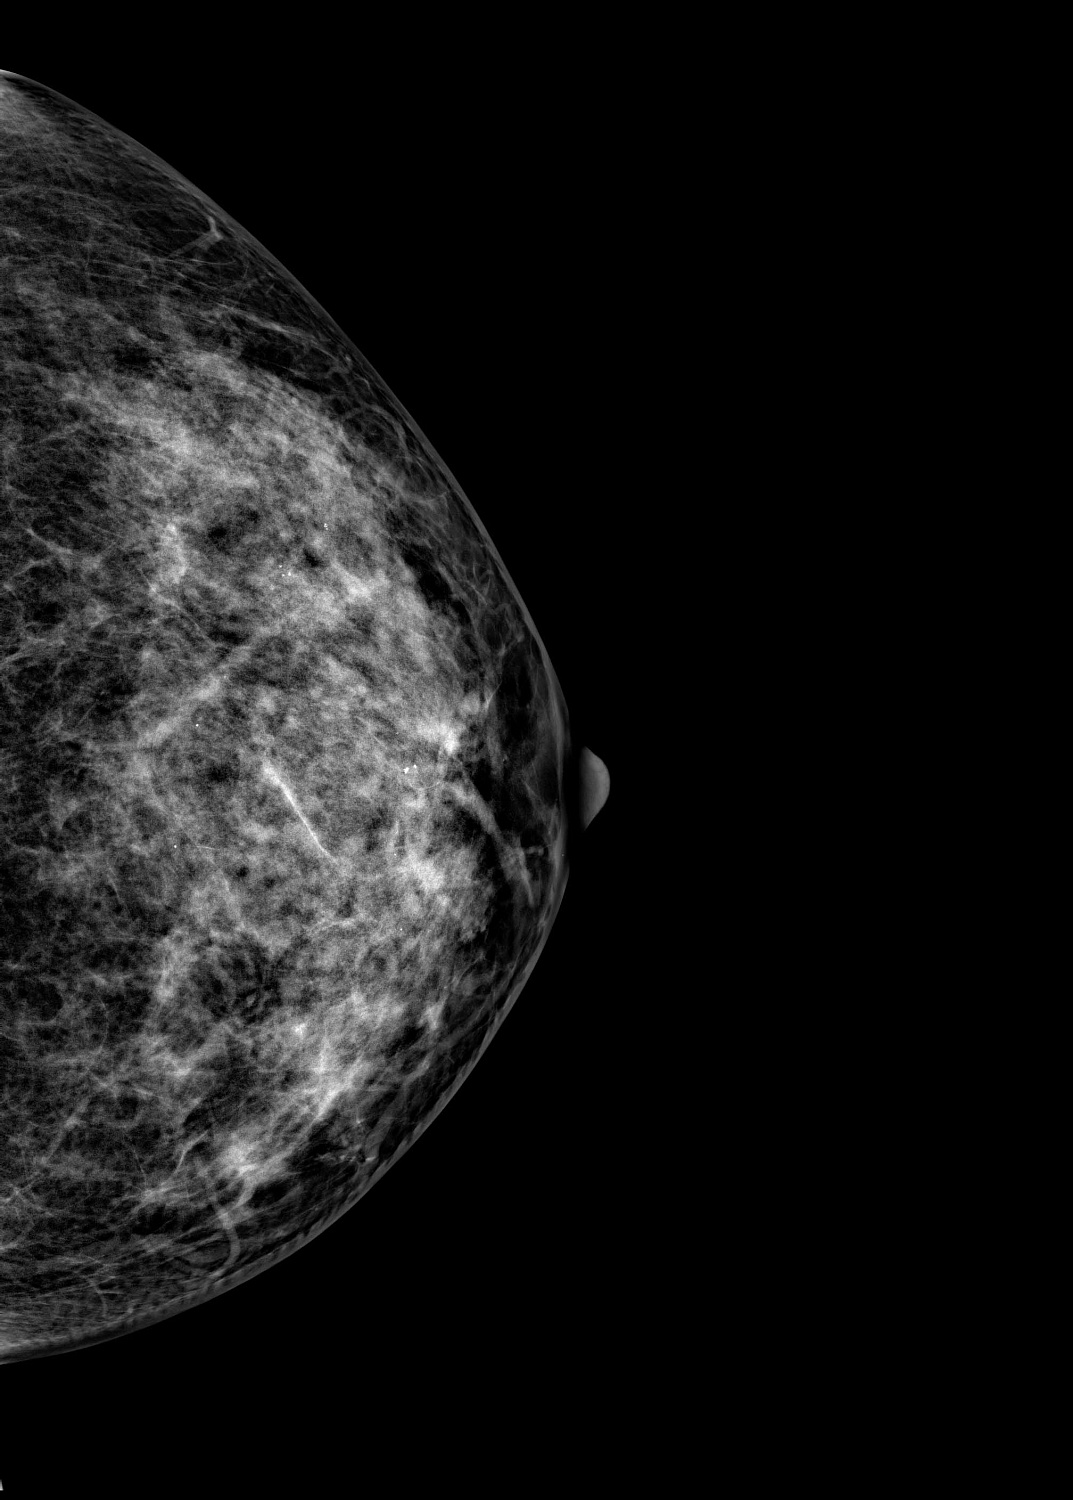

Маммограф выявляет опухоли молочной железы размером от 1-2 мм, которые не определяются при осмотре врача и самообследовании. На снимках хорошо различимы мельчайшие скопления солей кальция (от 87 мкм), тяжистые и другие перестройки тканей, характерные для рака груди 1-2 стадии. Высокую информативность, диагностическую ценность изображений обеспечивает цифровой детектор с самым чувствительным в мире сцинтиллятором. На снимках также определяются воспалительные процессы, кисты и даже небольшие повреждения.

Универсальный размер детектора делает обследование женщин с большим размером груди проще и безопаснее. Функция съемки молочных желез с имплантами позволяет обследовать эту категорию пациенток. На снимках хорошо различимы и ткани груди, и грудные эндопротезы.

Рентгеновский маммограф BRESTIGE EXPERT INDIRECT оснащен чувствительным сенсором непрямого преобразования на основе аморфного кремния. Цифровой детектор этого типа отличается надежностью и обеспечивает высокое качество изображения. Детальная «картинка» получается благодаря активной матрице, содержащей 2816 × 3584 пикселей, и хорошей квантовой эффективности (до 50%). На снимках ясно различимы даже небольшие изменения в структуре тканей и малоконтрастные образования.

Полноформатный детектор облегчает и ускоряет обследование женщин с большими молочными железами, а также делает его безопаснее. Пациенткам с грудью до пятого размера включительно для полноценного исследования достаточно 4 снимков: по 2 для каждой молочной железы. Аппараты, укомплектованные детектором меньшего размера, требуют 8 экспозиций.

Режим позволяет проводить маммографию у пациенток с грудными эндопротезами. На снимках хорошо видны ткани груди. Снимки отражают состояние импланта, в том числе его серьезные повреждения.